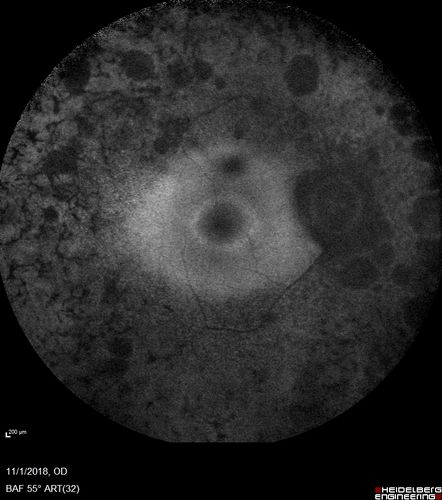

Retinitis Pigmentosa - Autosomal Dominant - Good Vision

55 year old female was diagnosed in 1990 with RP and the vision has been stable for the last 10 years.  Her mother and her two brothers and her grandmother and the patient and her two sisters all have confirmed RP.  No one has been tested. VA 20/25 OU